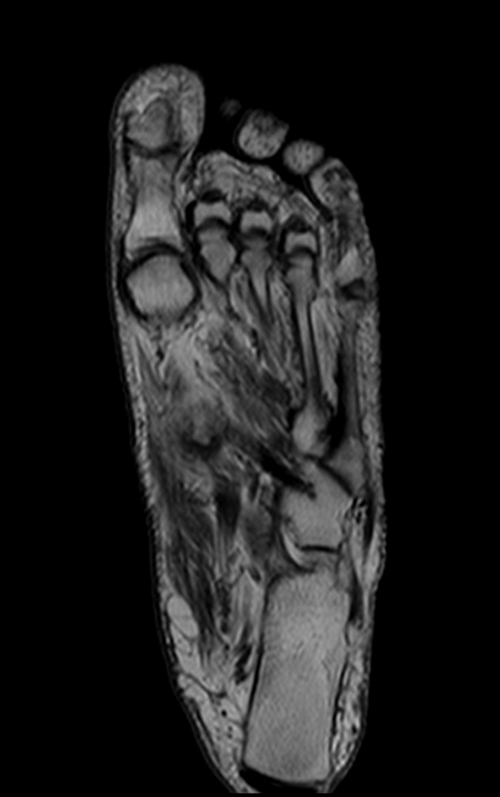

Mri Coronal View Foot . magnetic resonance (mr) imaging has opened new horizons in the diagnosis and treatment of many musculoskeletal diseases of the ankle and foot. standard axial, coronal and sagittal planes are used in the ankle both on 1.5t and in 3t. this anatomy atlas of the foot has been designed to help msk radiologists, rheumatologists and orthopedic surgeons in. high field strength 1.5t or 3t scanners and dedicated extremity coils. It demonstrates abnormalities in the bones and soft tissues before they become evident at other imaging modalities. an appropriate angle must be given in the coronal plane (perpendicular to the metatarsal and phalanges bones). In addition to the standard planes, a oblique scan is. magnetic resonance imaging (mri) is frequently required for accurate diagnosis given the broad spectrum of pathology and.

magnetic resonance (mr) imaging has opened new horizons in the diagnosis and treatment of many musculoskeletal diseases of the ankle and foot. standard axial, coronal and sagittal planes are used in the ankle both on 1.5t and in 3t. high field strength 1.5t or 3t scanners and dedicated extremity coils. this anatomy atlas of the foot has been designed to help msk radiologists, rheumatologists and orthopedic surgeons in. an appropriate angle must be given in the coronal plane (perpendicular to the metatarsal and phalanges bones). In addition to the standard planes, a oblique scan is. magnetic resonance imaging (mri) is frequently required for accurate diagnosis given the broad spectrum of pathology and. It demonstrates abnormalities in the bones and soft tissues before they become evident at other imaging modalities.